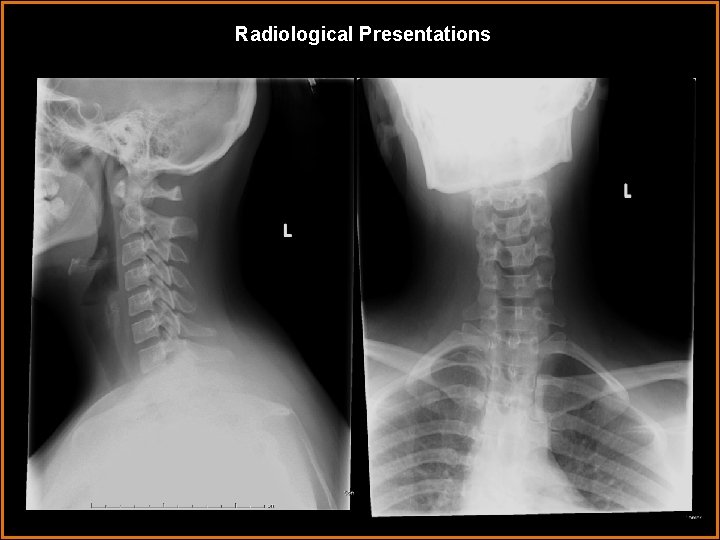

Case History 25 -year-old female with neck and lower back pain.

Radiological Presentations

Findings and Differentials Findings: -No acute abnormalities of the cervical spine. -Multiple vertebral segmentation anomalies with fusion of T 12 and L 1. Hypoplastic L 1 L 2 disc space with an L 2 hemivertebra. L 3 -4 fusion with no intervening disc. -Small posterior split of the spinal cord at T 11 progressing to two separate cords at L 1 within one dural sac with a bony/ligamentous septum at L 2 -3. The cords then fuse to form a normal-appearing conus at L 4, which is tethered with a filum terminale lipoma. -Narrowing of the left neural foramen at L 5 -S 1 related to facet hypertrophy. Differentials: • Diastatomyelia with low lying/tethered cord • Diplomyelia • Lipomyelomeningocele • Hydrosyringomyelia